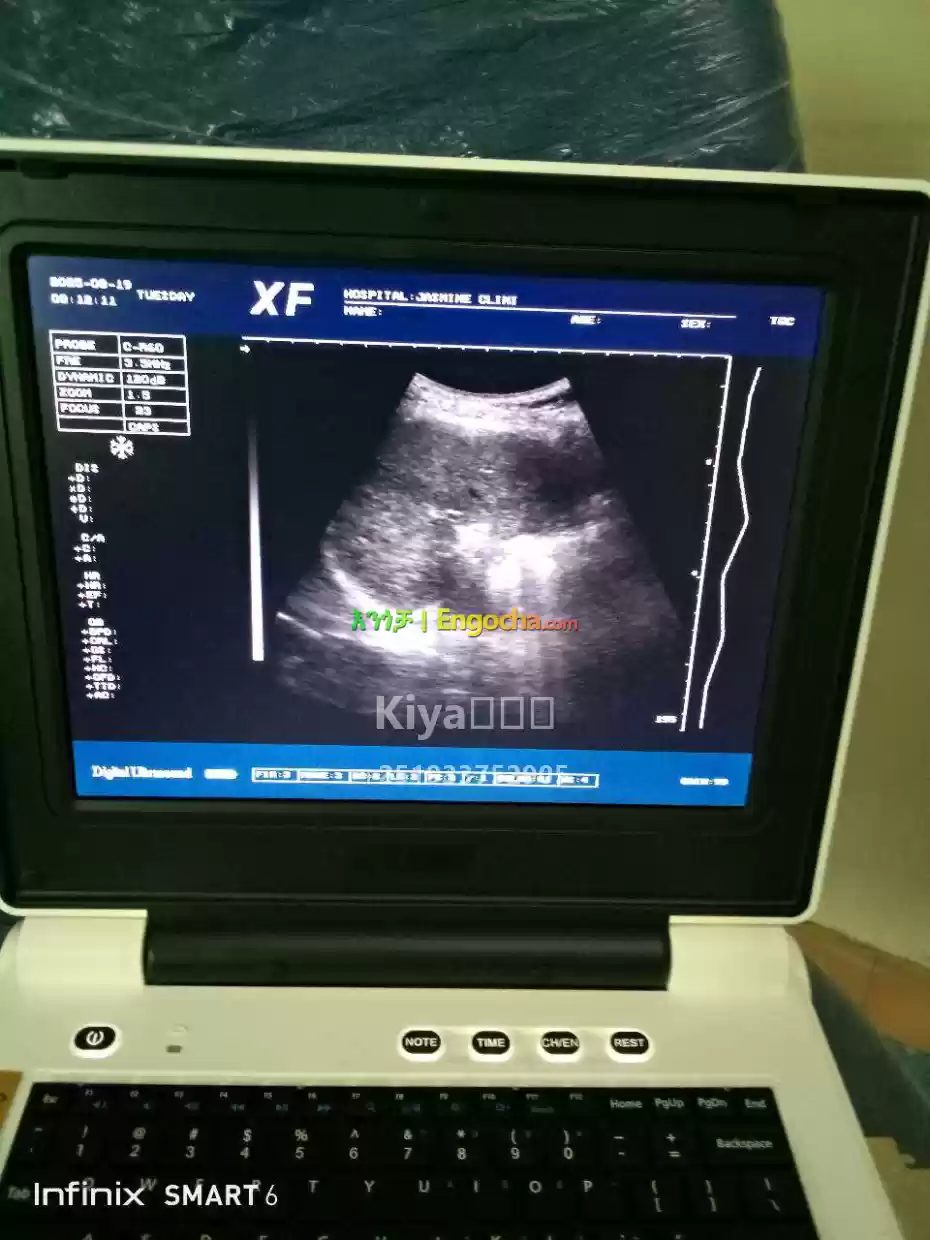

ultrasound machine items for sale and price in Ethiopia

Slightly used xf 30 B ultrasound machine with two probe